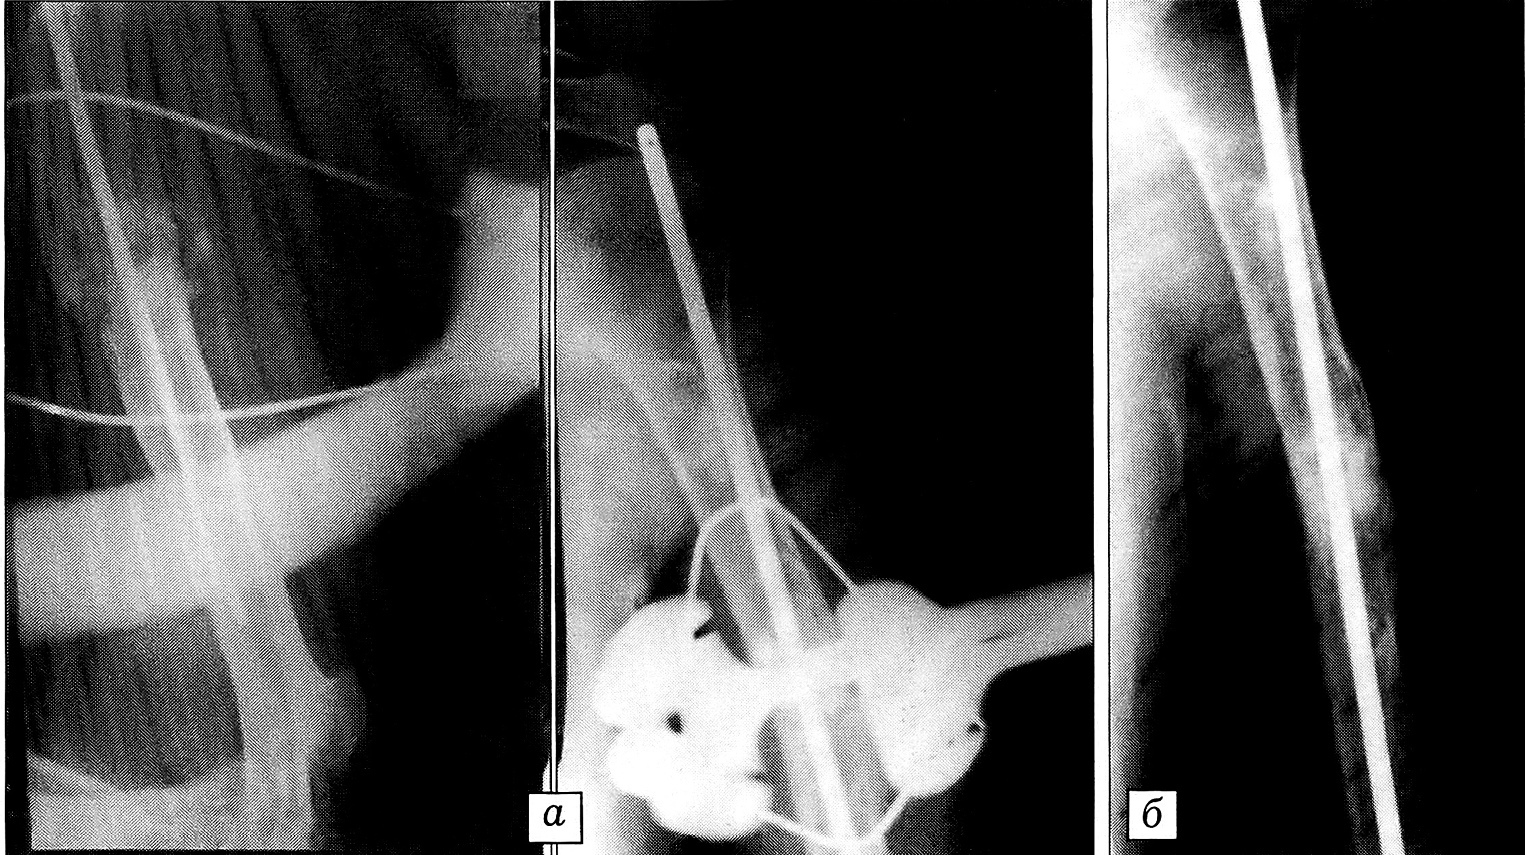

Рис. 5. Пример 5.Рентгенограммы больного Д.a — ложный сустав бедренной кости, контрактура коленного сустава через 8 мес после интрамедуллярного остеосинтеза штифтом;б — после наложения шарнирнодистракционного аппарата;в — спустя 8 мес: достигнуто сращение перелома и восстановление функции коленного сустава.

Пример 5. Больной Д., 45 лет, сбит автомобилем, получил закрытый перелом левой бедренной кости в средней трети. В лечебном учреждении вблизи места аварии произведен остеосинтез металлическим гвоздем. Перелом не сросся. Через 8 мес госпитализирован в ЦИТО для повторной операции. При поступлении: мышцы бедра атрофированы, движения в коленном суставе ограничены. Рентгенологически определяется ложный сустав бедренной кости (рис. 5, а). Без удаления гвоздя больному наложен шарнирно-дистракционный аппарат, произведена фиксация отломков с их взаимным давлением (рис. 5, б). Осуществлялась разработка движений в коленном суставе. Через 8 мес достигнуто сращение перелома и восстановление движений в коленном суставе (рис. 5, в).

Пример 6. Больной К., 52 лет, упал на руку, получил закрытый перелом правой плечевой кости. В больнице по месту жительства через 5 дней произведен остеосинтез металлическим штифтом. Штифт сломался, сращения перелома не наступило. При обращении в ЦИТО через 11 мес после травмы: мышцы правого плеча атрофированы, по наружной поверхности плеча имеются рубцы, на рентгенограммах — ложный сустав плечевой кости (рис. 6, а). Учитывая сложность ложного сустава, после удаления сломанного штифта в костномозговой канал плечевой кости вновь введен штифт и наложен шарнирно-дистракционный аппарат, при помощи которого осуществлялась фиксация костных отломков с взаимным давлением (рис. 6, б) с одновременной разработкой движений в локтевом суставе. Через 5 мес клинически и рентгенологически отмечено сращение перелома и восстановление движений в локтевом суставе. Аппарат удален (рис. 6, в).

Рис. 6. Пример 6.Больной К., ложный сустав плечевой кости через 11 мес после интрамедуллярного остеосинтеза штифтом, перелом штифта и смещение костных отломков.а — при поступлении в ЦИТО; б — произведены повторный остеосинтез штифтом, костная пластика, наложен аппарат наружной фиксации; в — через 5 мес: перелом сросся, функция локтевого сустава восстановлена.